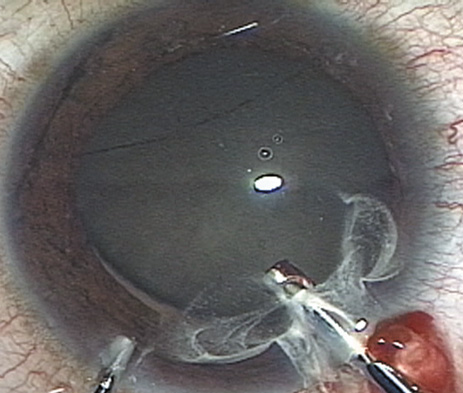

HYDRODISSECTION Hydrodissection can be performed after the surgeon has successfully completed capsulorrhexis.97 If the capsulorrhexis is not intact, fluid forced around the interior of the capsule may cause the bag to splay open. With capsulorrhexis, hydrodissection is a safe and extremely useful maneuver. Hydrodissection can be thought of as two maneuvers: hydrodelineation and cortical cleaving hydrodissection. By placing a 27-gauge cannula on a syringe filled with balanced saline solution (BSS), the surgeon can direct fluid beneath the residual anterior capsular rim to create a cleavage plane. Depending on the direction the fluid wave takes, different lamellae of the cataract will be separated. Hydrodelineation is the term used when the cleavage plane separates the adult nucleus from the fetal nucleus or the adult nucleus from the more peripheral epinucleus. Hydrodelineation often results in the characteristic golden ring sign (Fig. 11). Cortical cleavage occurs when the cortex is separated from the capsular bag (Fig. 12). Finding the cortical cleavage plane may be facilitated by gently lifting the capsular margin away from the cortex with the BSS cannula before injecting. Several small bursts of fluid allow the surgeon to monitor progress of the fluid wave. When dealing with a soft nucleus, the authors strive to perform true cortical cleaving hydrodissection. For a hard nucleus, hydrodelineation allows manipulation of less of the nuclear bulk, although the remaining epinuclear shell must be addressed in an additional step. Hydrodelineation is particularly useful if the nucleus is not freely mobile after cortical cleaving hydrodissection.